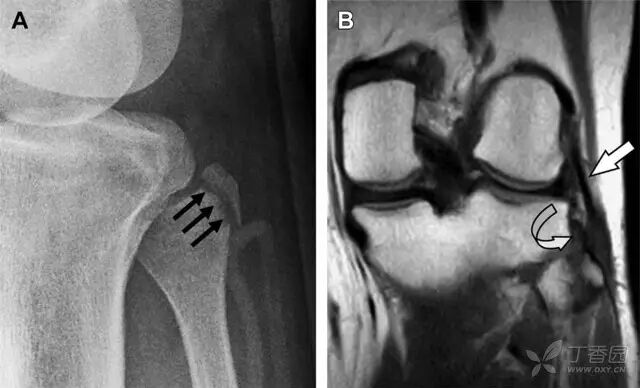

图 4 一位足球运动员的 Segond 骨折

A 正位片示关节线下方胫骨外侧皮质撕脱(箭头)。B MRI 冠状位 T1 加权像示附着于髂胫带的骨折碎片(空箭头)。

Segond 骨折是发生在胫骨平台外侧的垂直撕脱性骨折(图 4)。这种骨折在前后位 X 线片上显示最佳。

屈曲位时膝关节受到内旋暴力作用,导致皮质骨撕脱性骨折,这种骨折常发生在运动员身上。常引起股骨内髁和胫骨平台后内侧骨挫伤,75%~100% 的患者伴前交叉韧带断裂,33% 的患者伴外侧半月板损伤。